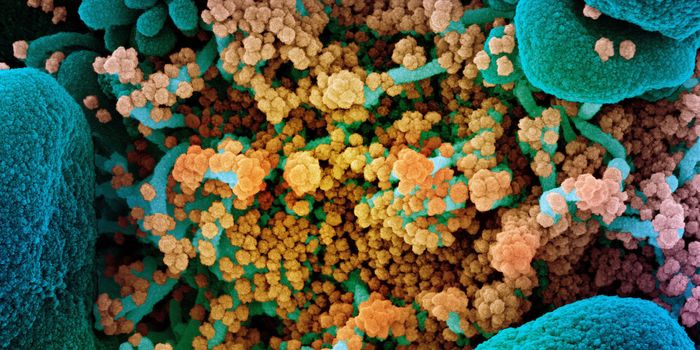

MAR 14, 2022ImmunologyThough it may happen at different rates for different microbes, mutations happen, and SARS-CoV-2, the virus that causes ...

NOV 26, 2021MicrobiologyOn Thursday, November 2021, South African health officials announced that they had identified a new variant of the pande ...

NOV 01, 2021Cell & Molecular BiologyResearchers have learned a lot about the SARS-CoV-2 virus since the start of the COVID-19 pandemic. We know that he viru ...